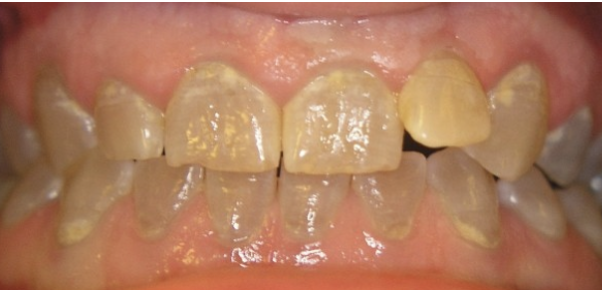

Welke typen amelogenesis imperfecta zijn er?

Hypoplasie en hypocalcificatie.

Wat is hypoplasie?

Hierbij is er een onvolledig ontwikkeld glazuur. Er was dus een stoornis in de vorming.

Wat is hypocalcificatie?

De vorming zelf is normaal maar er is een stoornis in de calcificatie. Er is iets fout gegaan bij de ameloblasten, die dit opbouwen. De vormins is goed maar er mist iets in de mineralisatie.